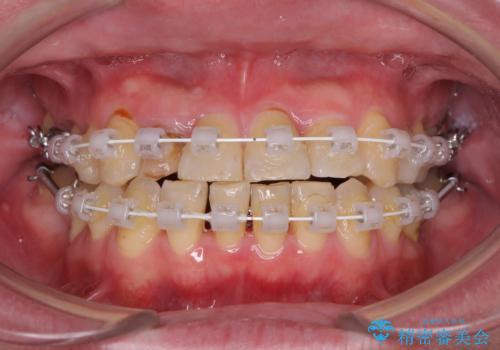

- 矯正装置

- 審美装置

- 治療期間

- 3年10ヶ月